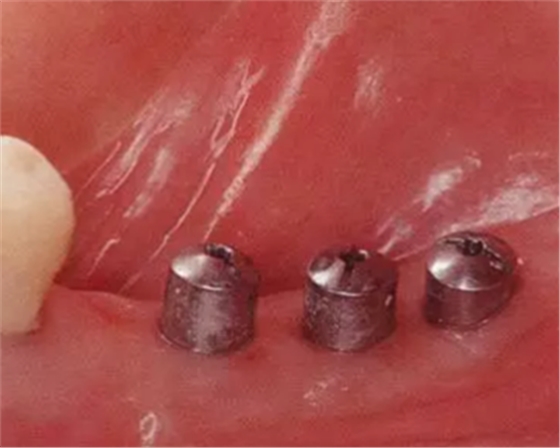

Type3-Class2

的病例(病例8):種植體植入后,由于覆蓋螺絲露出導(dǎo)致角化齦喪失,在第二次手術(shù)時頰舌側(cè)進行FGG的病例。

▲圖10-1,2

圖10-1 頰側(cè)和牙槽嵴有角化齦的存在,但是愈合期間內(nèi)覆蓋螺絲露出(Type3-Class2)